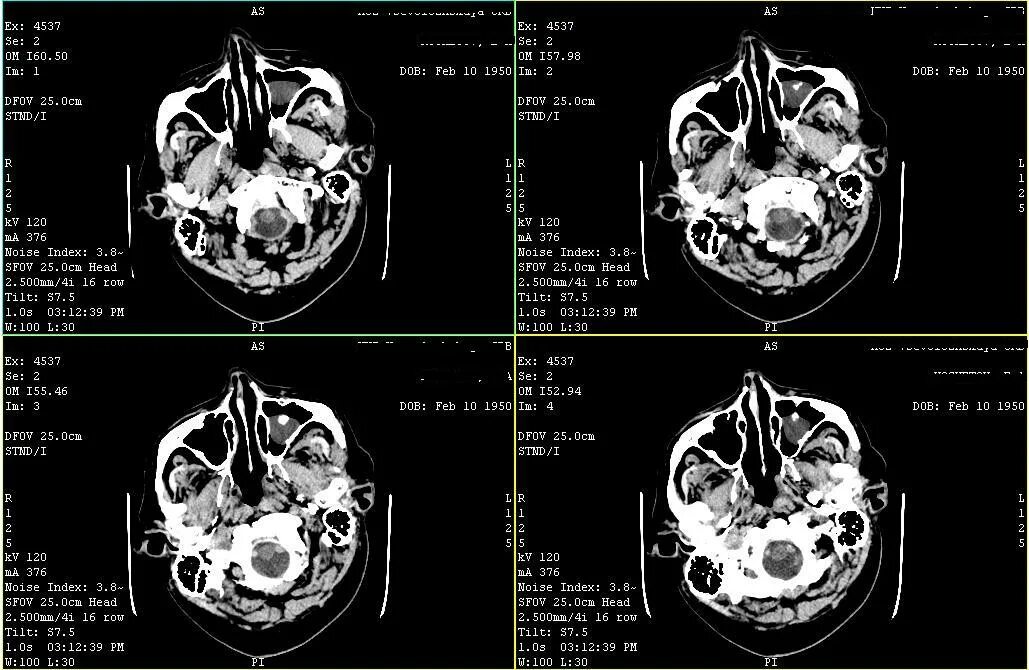

Кт пример